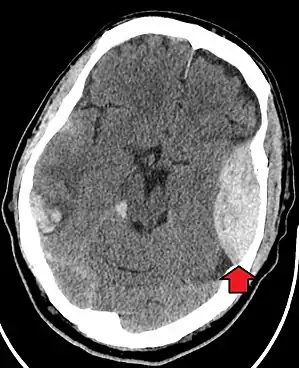

Blunt cranial trauma

The primary clinical concern with blunt trauma to the head is damage to the brain, although other structures, including the skull, face, orbits, and neck are also at risk.[9] Following assessment of the patient's airway, circulation, and breathing, a cervical collar may be placed if there is suspicion of trauma to the neck. Evaluation of blunt trauma to the head continues with the secondary survey for evidence of cranial trauma, including bruises, contusions, lacerations, and abrasions. In addition to noting external injury, a comprehensive neurologic exam is typically performed to assess for damage to the brain. Depending on the mechanism of injury and examination, a CT scan of the skull and brain may be ordered. This is typically done to assess for blood within the skull, or fracture of the skull bones.[18]

Traumatic brain injury

Traumatic brain injury (TBI) is a significant cause of morbidity and mortality and is most commonly caused by falls, motor vehicle crashes, sports- and work-related injuries, and assaults. It is the most common cause of death in patients under the age of 25. TBI is graded from mild to severe, with greater severity correlating with increased morbidity and mortality.[18][19]

Most patients with more severe traumatic brain injury have of a combination of intracranial injuries, which can include diffuse axonal injury, cerebral contusions, and intracranial bleeding, including subarachnoid hemorrhage, subdural hematoma, epidural hematoma, and intraparenchymal hemorrhage.[9][18] The recovery of brain function following a traumatic injury is highly variable and depends upon the specific intracranial injuries that occur, however there is significant correlation between the severity of the initial insult as well as the level of neurologic function during the initial assessment and the level of lasting neurologic deficits.[18] Initial treatment may be targeted at reducing the intracranial pressure if there is concern for swelling or bleeding within this skull, which may require surgery such as a hemicraniectomy, in which part of the skull is removed.[9][18]